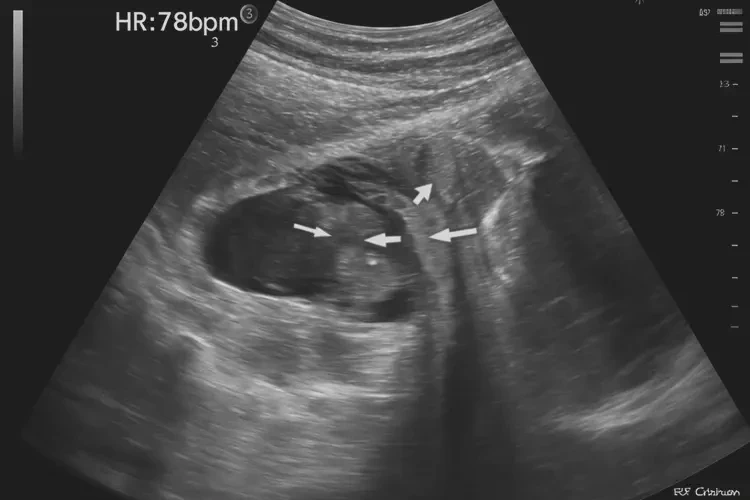

胎心率79次/分钟 在孕18周3天的情况下属于较低水平。正常胎心率范围为120-160次/分钟,低于120次/分钟可能提示胎心过缓。

胎心率是评估胎儿健康状况的重要指标之一。在孕18周3天时,胎儿的心脏已经发育成熟,能够通过胎心监护仪进行监测。正常情况下,胎心率应保持在120-160次/分钟之间,这表明胎儿的心脏功能正常,血液循环良好。当胎心率低于120次/分钟时,可能存在胎心过缓的情况,需要引起重视。

孕18周3天胎心率79次/分钟属于较低水平,可能提示胎心过缓。如果发现胎心过缓,应及时就医,进行详细检查和治疗,以确保胎儿的健康。